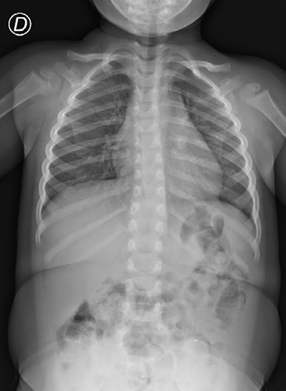

El estudio radiográfico de tórax mostró una pequeña imagen radio opaca en la topografía del lóbulo superior del pulmón derecho en la proyección anteroposterior (Fig. 1A). Se identificó una imagen similar a nivel de la tráquea cervical en la radiografía de perfil de la columna cervical (Fig. 1B). La radiografía abdominal, en la topografía de la cámara gástrica, mostró pequeñas imágenes radio opacas, compatibles con trazas de un objeto metálico (Fig, 1C).

FUENTE: Autores.

FIGURA. 1 Radiografía de Tórax (AP): imagen radio opaca lineal en el lóbulo superior del pulmón derecho; B. Radiografía de columna cervical (perfil): imagen similar a nivel de la tráquea cervical; C. Radiografía abdominal (AP): imágenes topográficas radio opacas de la cámara gástrica.

Durante la evaluación pre-anestesia, debido a la falta de signos clínicos compatibles con ACE en un paciente con historia de hiperresponsividad bronquial, se cuestionó la posibilidad de error en la adquisición / interpretación de la imagen. Luego de conversar con el radiólogo, se llevó a cabo un nuevo estudio radiográfico digital directo, sin imágenes compatibles con cuerpos extraños (Fig.2). Los hallazgos iniciales se consideraron artefactos y no se realizó la broncoscopia rígida.